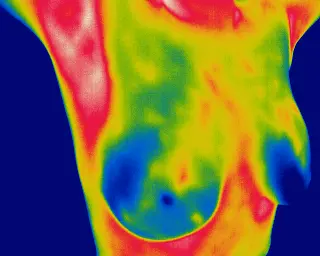

The Breast Health Revolution

Breast Thermography with Thermo Check

Advanced thermography for detecting risks at the earliest stage

Painless imaging with no radiation, ensuring client safety and comfort

Deep painless detection

Thermography detects the vascular changes in the blood vessels that are going to feed an early tumour, between 6 -10 years earlier than you would notice on a mammogram. So by that time the tumour is already quite advanced and may well have started metastasising – that’s spreading to other parts of the body; that is not a great balance – you are already eradiating the tissue and then you are offering them a much lower chance of full recovery and survival because it is much later in the process.*

Thermography picks up at a much earlier stage, when the blood vessels are already growing to feed the tiny tumour at a much earlier stage than the mammography process does so early breast screening is really important.*